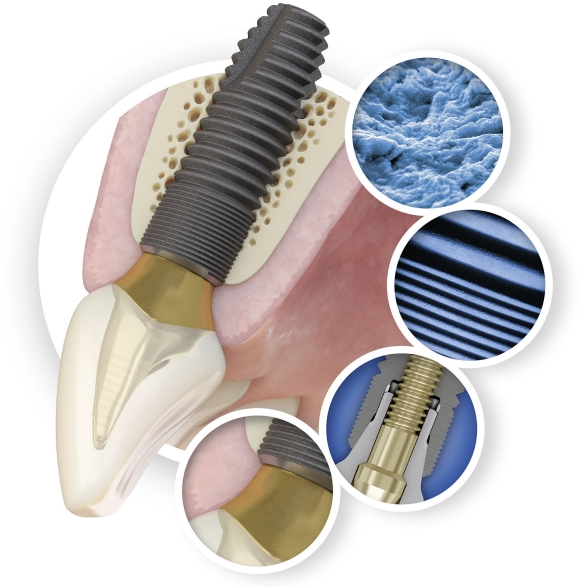

Het behoud van marginaal bot is de basis voor het succes van een tandheelkundig implantaat en een belangrijke factor voor het esthetische resultaat.

Het ongeëvenaarde marginale botbehoud van Astra Tech Implant System EV zorgt voor:

Levenslange functie

— een kans om te eten, te drinken en te leven zonder u zorgen te maken over de tanden.

Natuurlijke esthetiek

— de vrijheid om een mooie glimlach te tonen en met volle teugen van het leven te genieten.